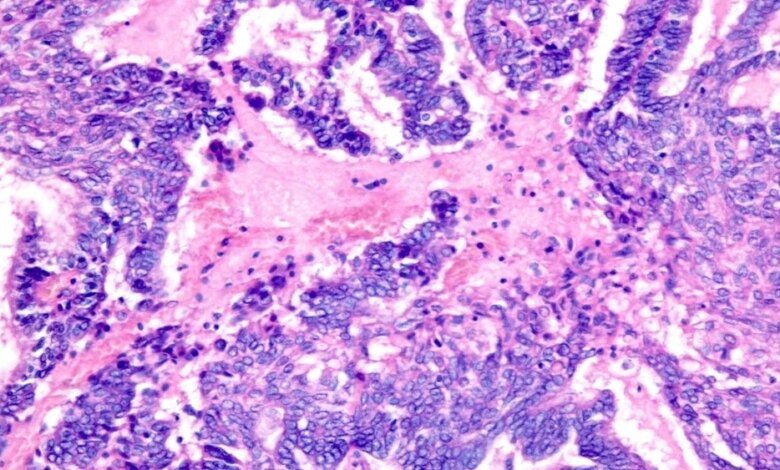

وتعتمد هذه الطريقة على حقيقة أن الريبوفلافين يرتبط بالحمض النووي والحمض النووي الريبوزي (RNA)، وعند تعريضه للأشعة فوق البنفسجية، فإنه يدمر المادة الوراثية للفيروسات والبكتيريا والطفيليات، مما يحرمها من القدرة على التكاثر. جاءت فكرة الاستخدام لعلاج الأورام من الكيميائي راي جودريتش في جامعة ولاية كولورادو. ولاحظ أنه بعد العلاج بالأشعة فوق البنفسجية، تفقد الخلايا قدرتها على الانقسام، لكنها تحتفظ ببنيتها.

ووفقاً لخطته، يمكن تحويل الخلايا السرطانية “المعطلة” لدى المريض إلى لقاح شخصي: فهي لا تشكل ورماً، ولكنها تحتوي على جميع المستضدات الجديدة – بروتينات الورم الفريدة التي يتعرف عليها الجهاز المناعي.

يمكن لهذا النهج أن يحل إحدى المشاكل الرئيسية للقاحات السرطان – الحاجة إلى التخمين مقدمًا أي المستضدات ستكون أكثر فعالية. إن تضمين الخلايا الكاملة يزيد من فرص النجاح.